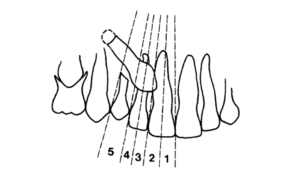

Determinação dos setores para avaliação do posicionamento dos caninos

Uma primeira avaliação deve ser realizada tomando-se como base a linha média e as paralelas a ela passando pelos pontos de contato entre os incisivos e o seus longos-eixos e estendendo-se até o canino decíduo. Essas paralelas determinam 5 setores. A visualização da ponta do canino entre os setores 1 a 3 indicam maior a possibilidade de reabsorção das raízes dos incisivos e a probabilidade aumenta quanto mais próximo do setor 1 estiver o canino.